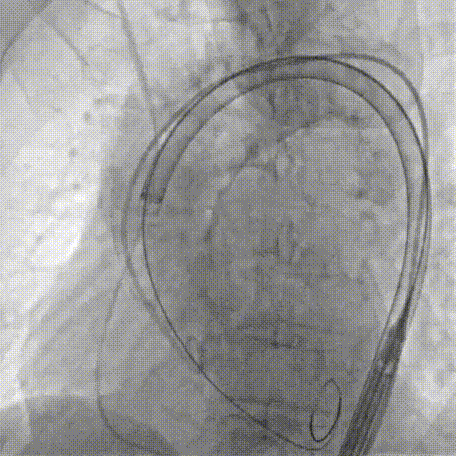

Step 8.最终造影:真实瓣环下方3mm标准位,完全同轴,轻微反流,猪尾撤出后反流完全消失

Step 9.CuspOverlap体位验证缘对缘对齐,挂钩位于最右方,基本避开冠脉开口

Step 10.验证器械同轴性,完全同轴